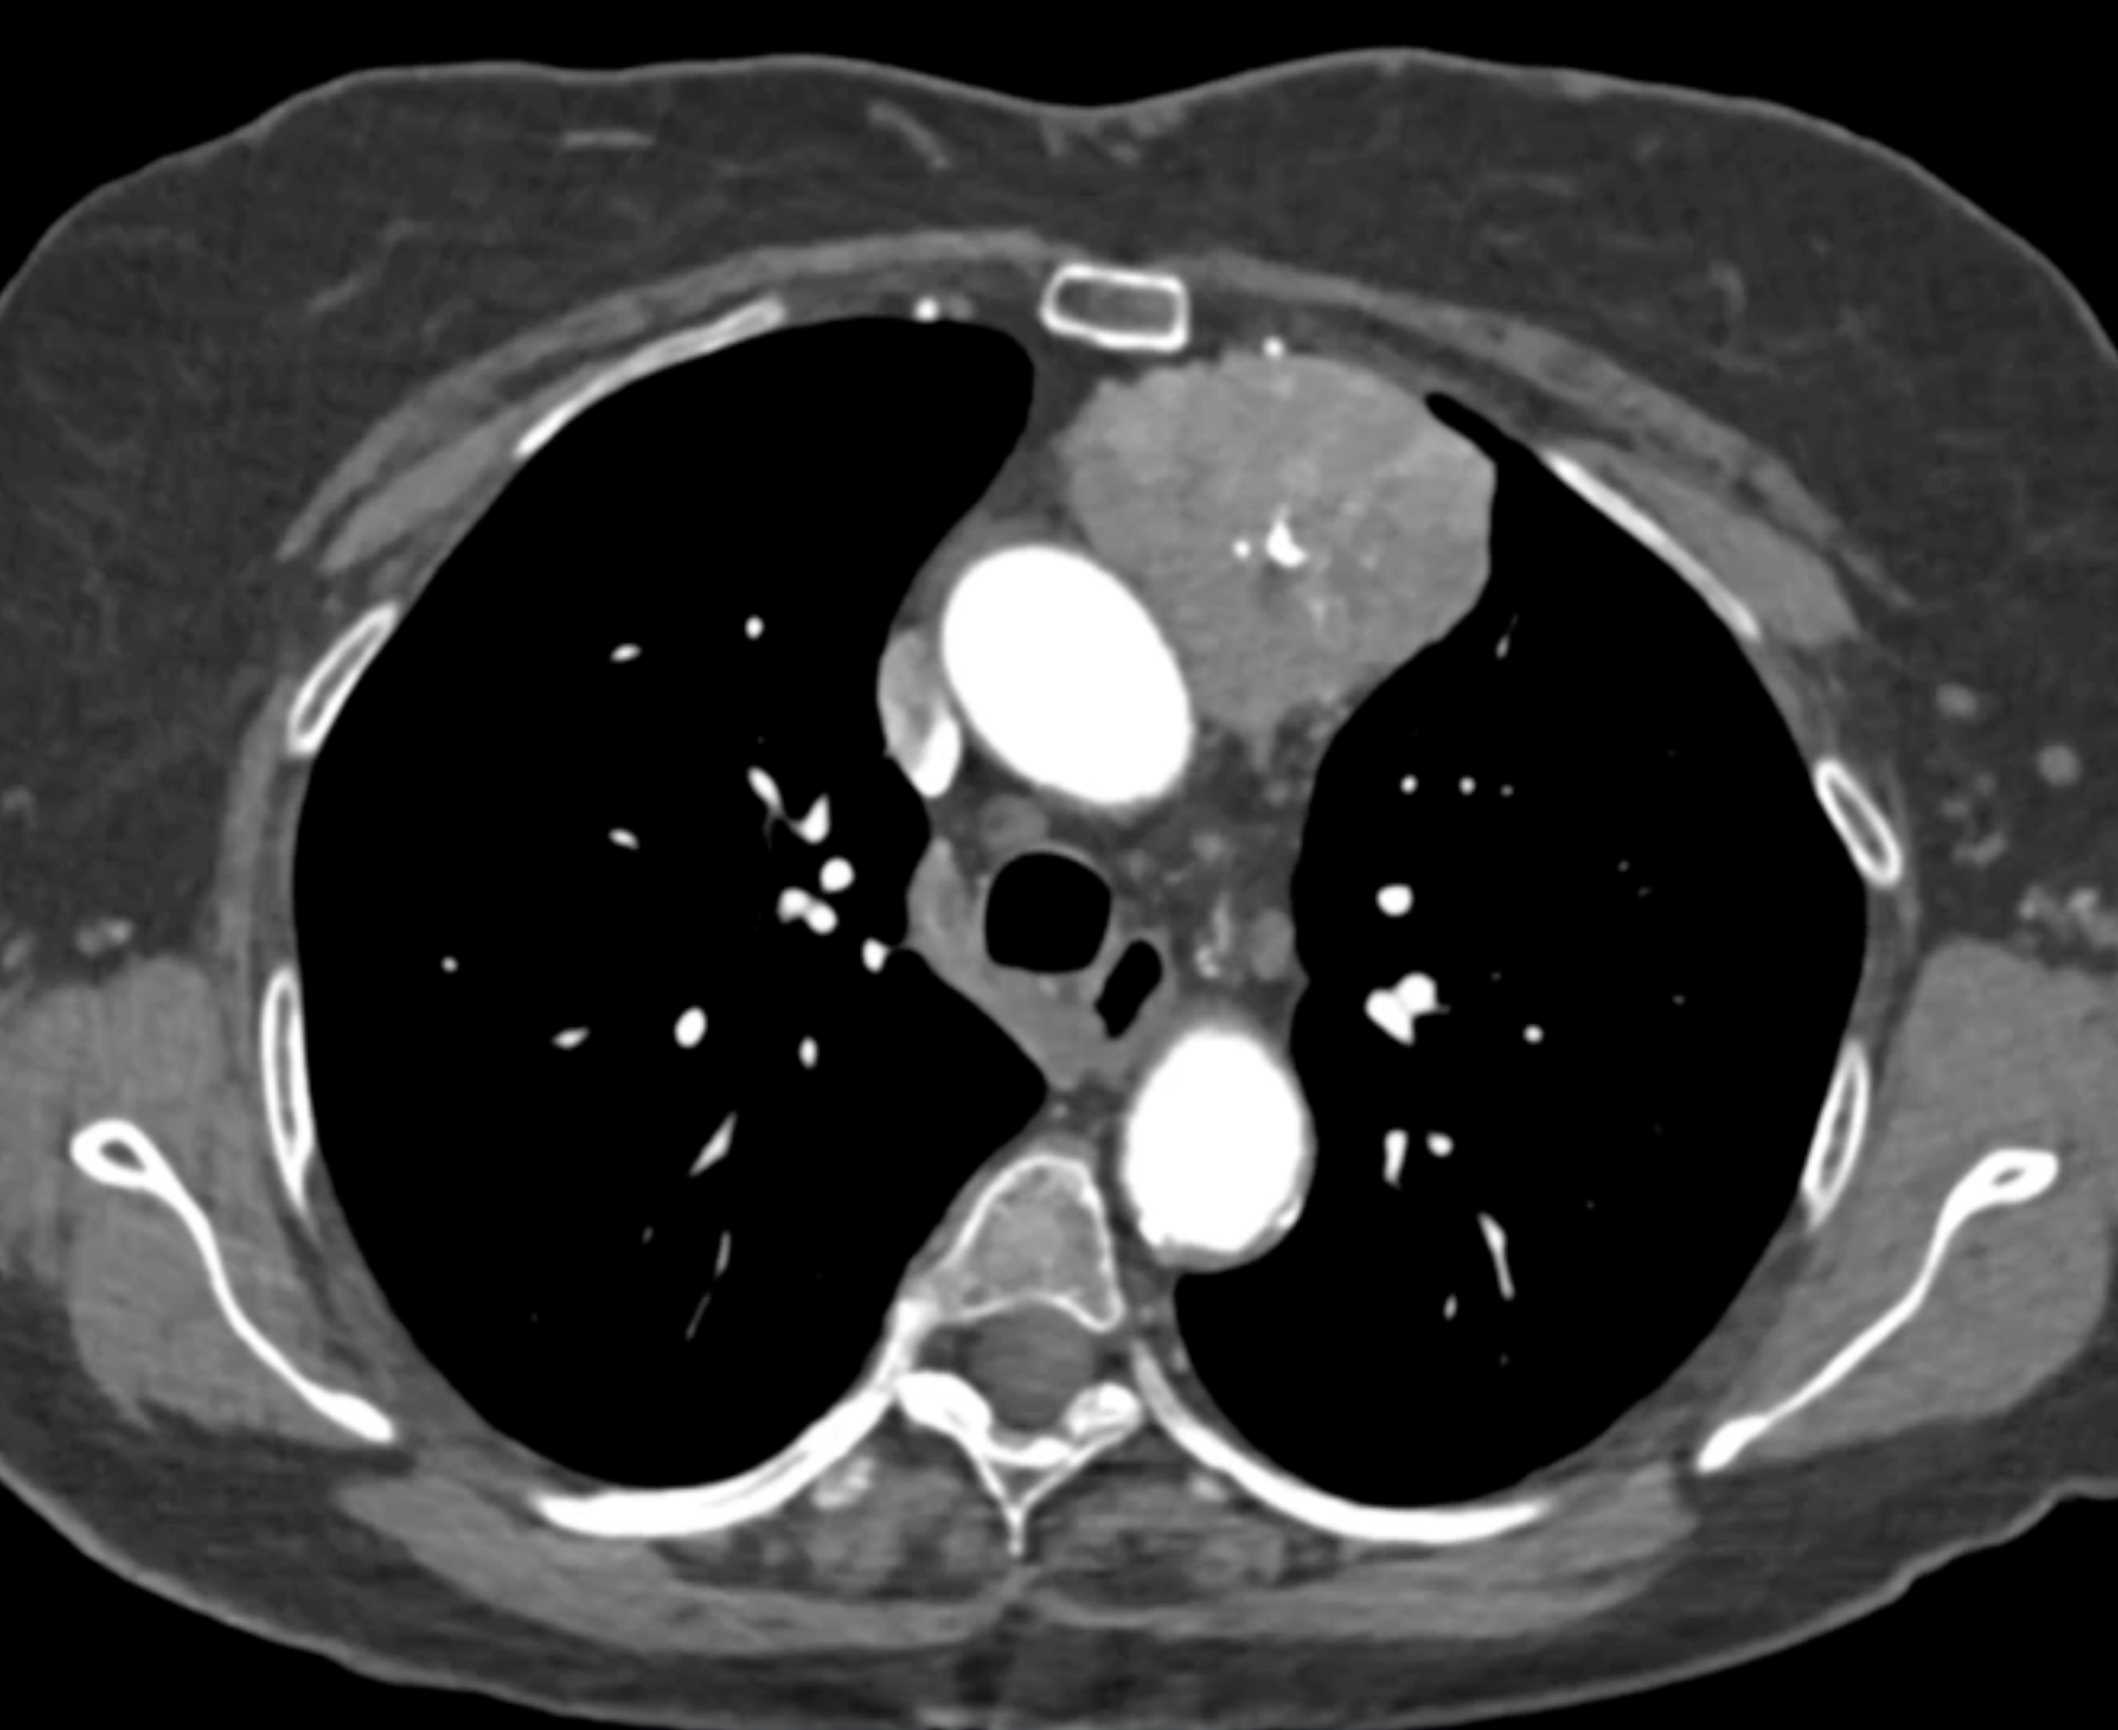

Thymic Carcinoma